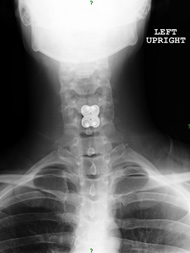

I had some diagnostic injections that helped point to the C4-5 level as the source of most of my pain. The injections gave me more than enough information to proceed with the C4-5 fusion. I also had a questionable pseudarthrosis (fracturing that won’t heal without intervention) at the C7-T1 level. Dr. Jatana recommended doing the C4-5 surgery first and waiting to see if the C7-T1 pseudarthrosis was still problematic after I recovered. There wasn’t a quick or easy solution for me and I really appreciated that Dr. Jatana conveyed to me that patience was part of my treatment plan.

Dr. Jatana operated on me in September 2013. The crushing pain on top of my shoulders and the nerve root pain that I was experiencing was better immediately after surgery. I’m able to work and exercise now. I am getting stronger every day and am able to do things that I haven't been able to do for years.